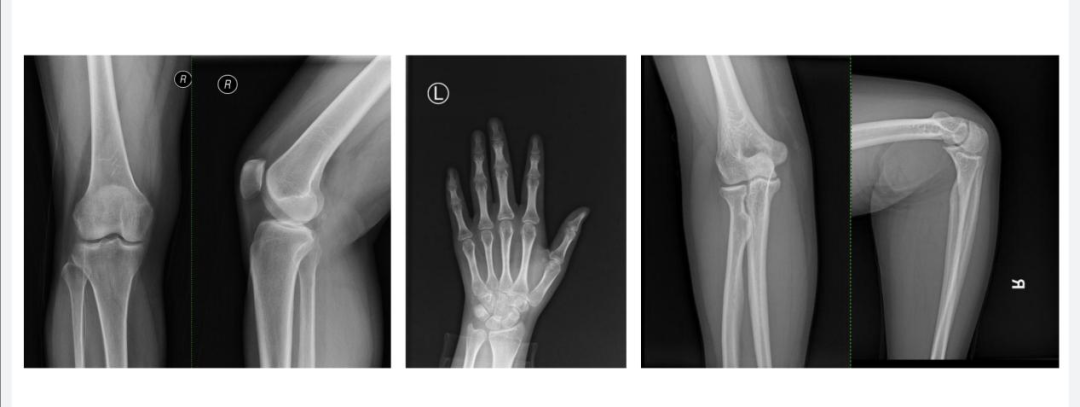

DR:简单快捷的“拍片子”

说起DR,可能大家更熟悉它的俗称“拍片子”。它利用X线技术,通过影像增强管接收信息,再转换成数字信号,形成清晰的图像。就像给身体拍了个平面照,骨骼、肌肉、水分等不同成分在X线下的“身影”各不相同,从而呈现出灰阶图像。DR检查价格便宜,速度快,辐射小,特别适合作为初步筛查,尤其是骨科疾病的诊断。